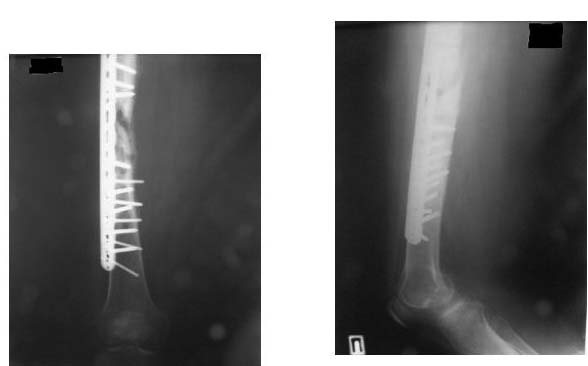

Результат нашего лечения: Произведено удаление пластины МIPO. Интрамедуллярный остеосинтез с рассверливанием канала. На 2-е сутки после операции больная передвигается при помощи костылей, с полной нагрузкой на оперированную конечность, болей в области перелома нет.

Фотографии в приложении.

Еще раз спасибо за советы!

Непонятно, нога вроде как правая. ... С проксимальным блокированием вопросов нет. А что, дистальное блокирование делали изнутри кнаружи (смотрю по ориентации снимков)? Зачем???